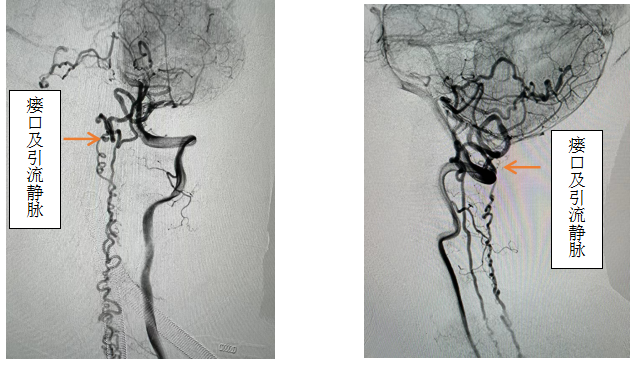

患者女性,56岁,以“双下肢无力伴感觉异常半年,加重2月”主诉入院,入院前先后辗转我省多家医院,效果欠佳。入院时已经行走困难,行颈椎核磁见颈椎蛛网膜下腔异常信号影,请神经外科会诊后考虑硬脊膜动静脉瘘可能性大,转入神外后立即由李帅主治医师行全脊髓血管造影,见“左侧椎动脉V4段发出脑膜支,其远端分支供血形成硬脊膜动静脉瘘,瘘口位于枕骨大孔区,经延髓背侧及腹侧向下引流至胸2椎体节段”。缪星宇主任主持全科病例讨论,讨论考虑患者经脊髓血管造影后诊断明确,手术指征明确,可行硬脊膜动静脉瘘介入栓塞术或开颅阻断术。术中可采取“高压锅”技术防止栓塞胶的返流,降低微导管的到位要求,降低返流空间的要求,使得返流空间安全可控,缩短注胶时间,增加胶的弥散效率,从一定程度上提高栓塞比例,增加患者的安全性。如介入微导管到位困难,可以考虑开颅阻断瘘口,但瘘口位置距离呼吸中枢延髓较近、术中风险大且术后患者恢复时间长。科室讨论后决定利用五楼自拍

先进的复合手术室,首先采用第一方案“高压锅”技术使胶完全封堵瘘口,若不能到位或完全封堵,则采用第二方案,转为开颅阻断瘘口。手术当日,由黄卫东主任医师和李帅主治医师操作,第一根栓塞微导管顺利到达瘘口,第二根微导管接近栓塞微导管后使用弹簧圈顺利形成高压锅塞子,经第一根微导管注入栓塞胶,射线透视下见栓塞胶按预期流向瘘口,栓塞满意后造影示瘘口及引流静脉均未见显影,手术成功。术后患者恢复良好,第二天即下床活动,下肢活动明显恢复,5天后步行出院。